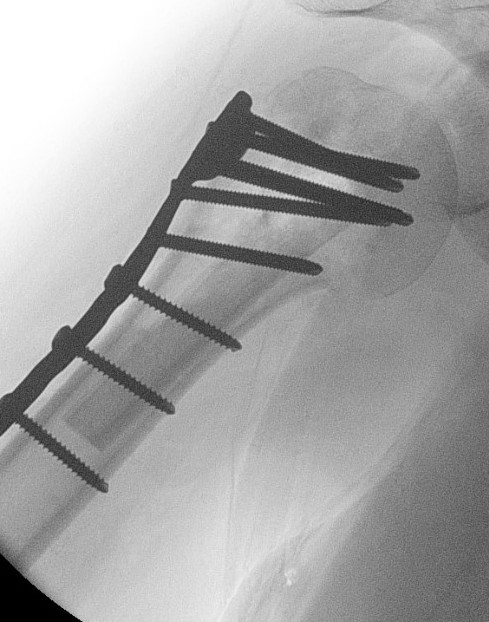

ORIF with locking plate

Apply plate

- lateral to biceps with single cortical screw in oblique hole

- check fluoroscopy - avoid having plate too high

- keep head out of varus to avoid cutout

- long inferomedial screws / kickstand screws

- locking screws

Plates

Long proximal humerus plates